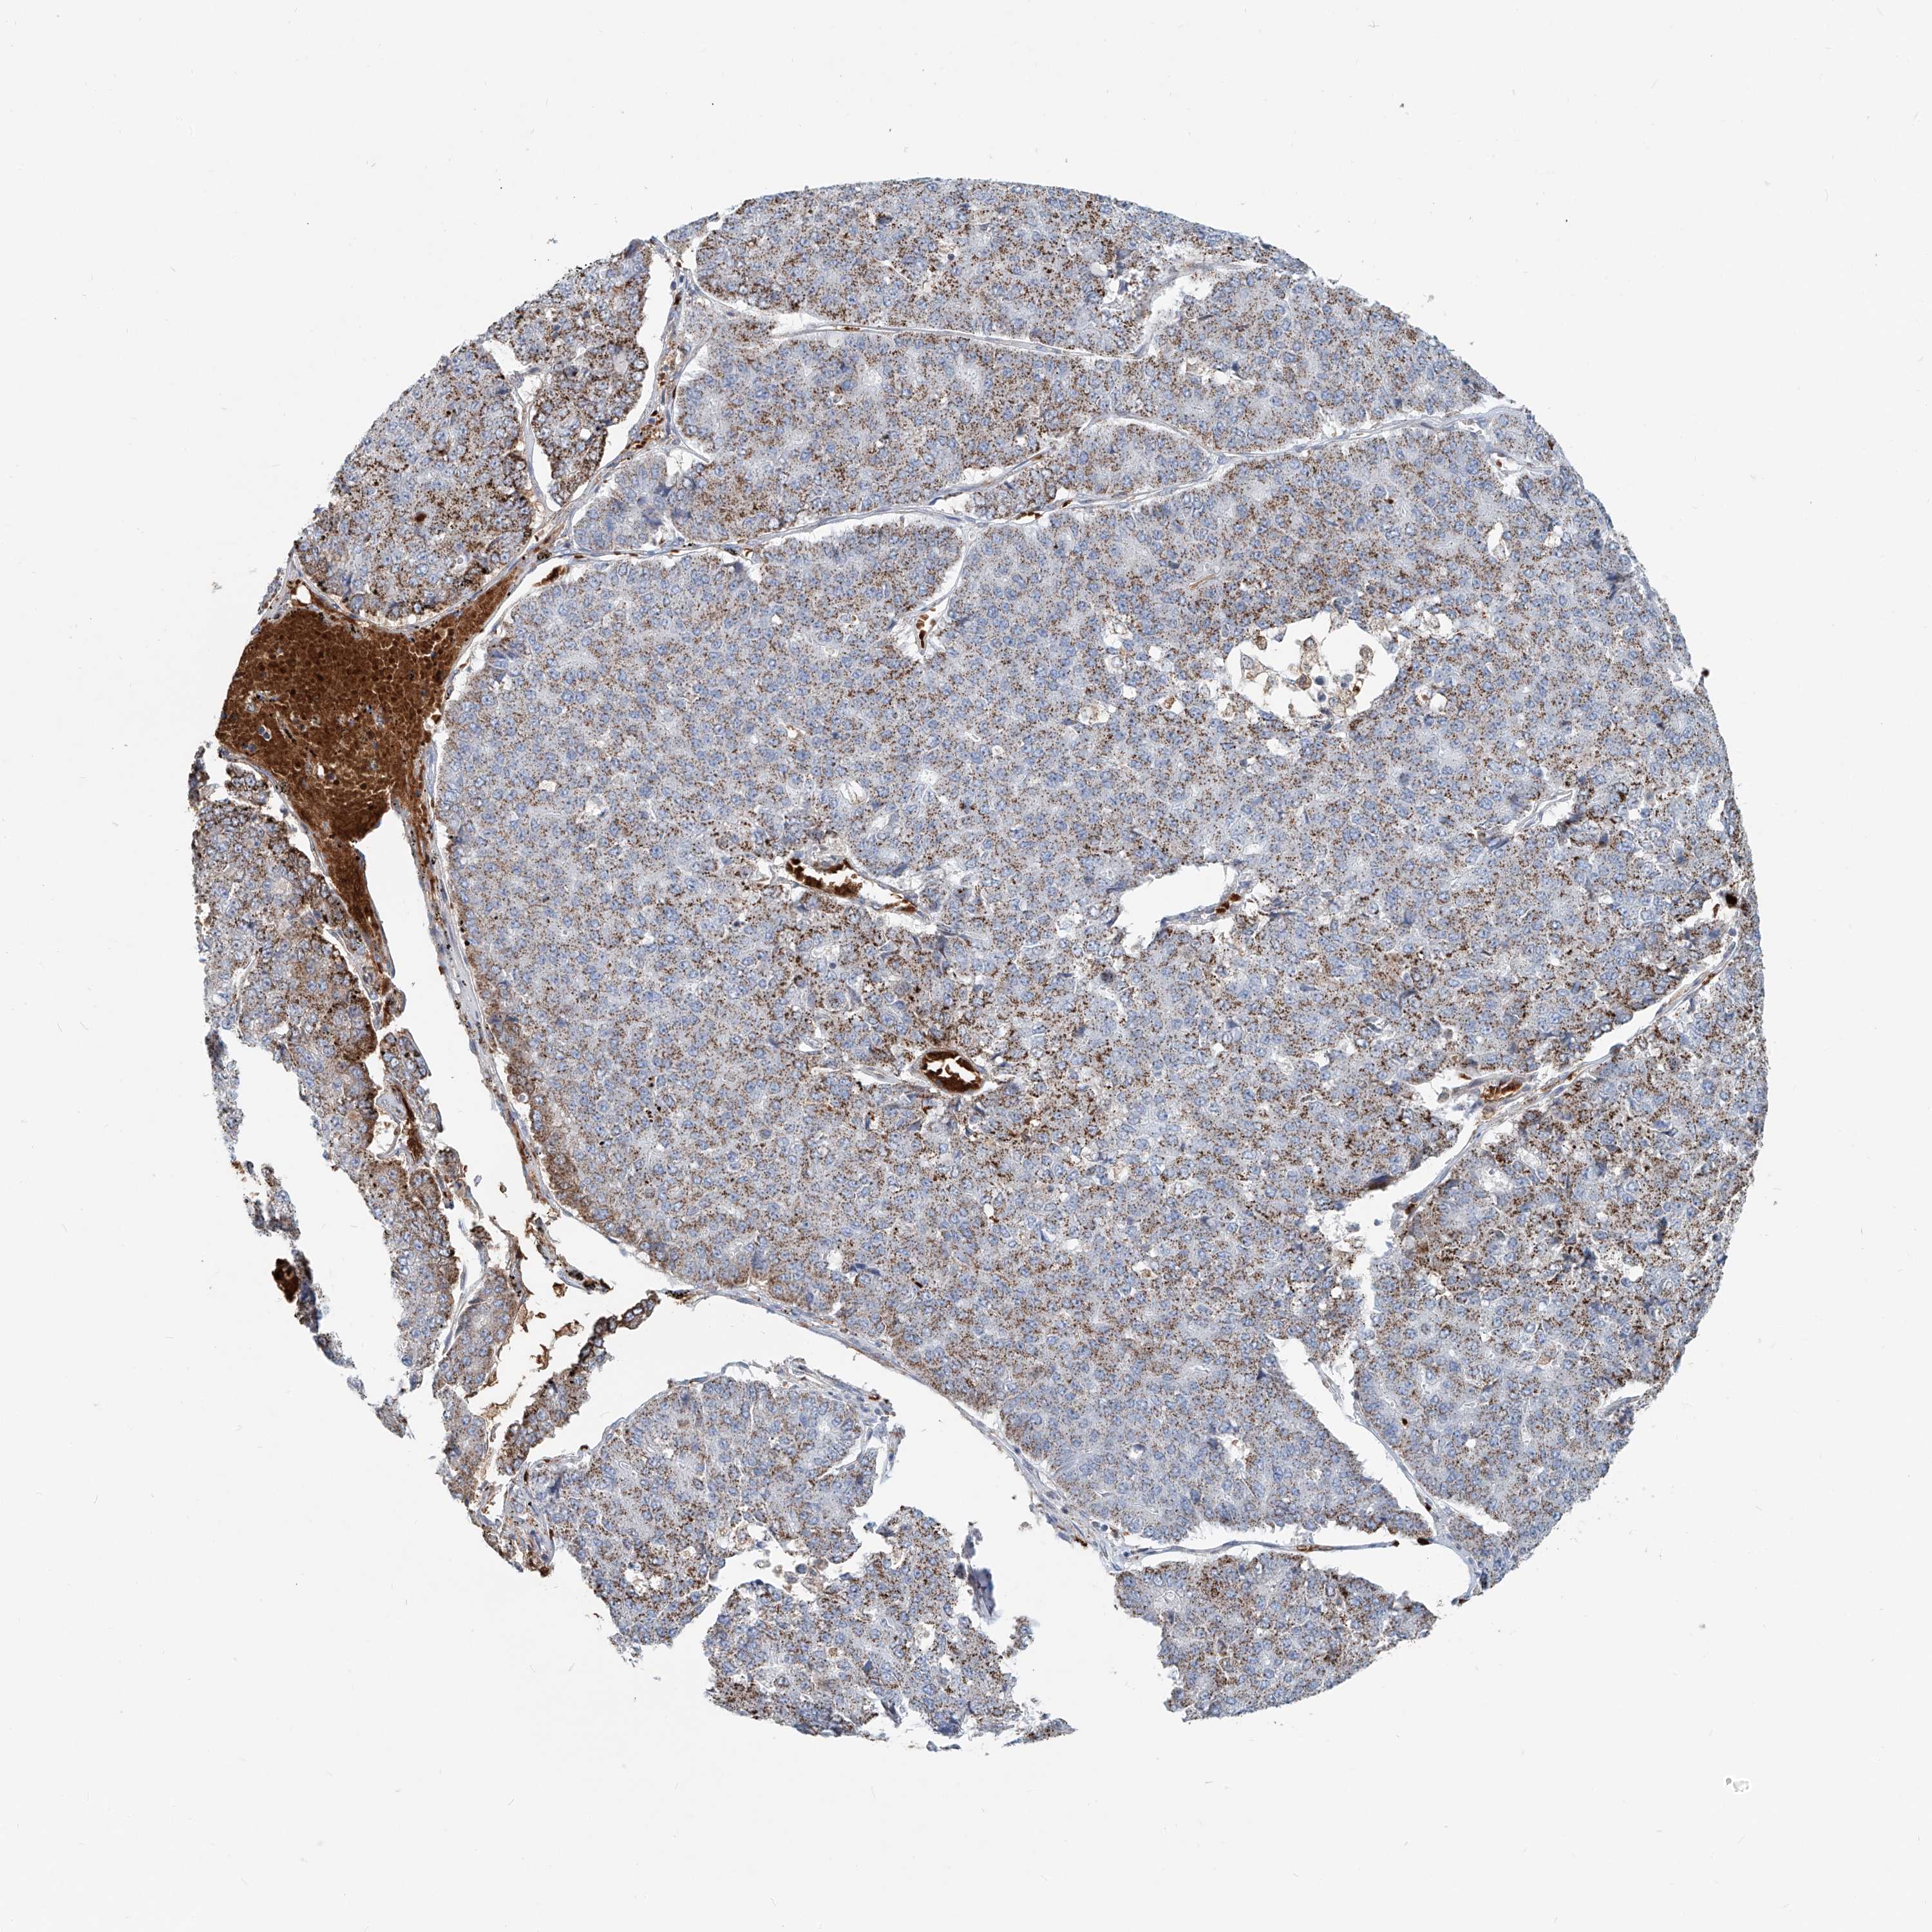

PANCREATIC CANCER - Protein expressioni

A mouse-over function shows sample information and annotation data. Click on an image to view it in a full screen mode. Samples can be filtered based on level of antibody staining by selecting one or several of the following categories: high, medium, low and not detected. The assay and annotation is described here.

Note that samples used for immunohistochemistry by the Human Protein Atlas do not correspond to samples in the TCGA dataset.

Antibody stainingi

Antibody staining in the annotated cell types in the current human tissue is reported as not detected, low, medium, or high, based on conventional immunohistochemistry profiling in selected tissues. This score is based on the combination of the staining intensity and fraction of stained cells.

Each image is clickable and will lead to virtual microscopy that enables deeper exploration of all samples and also displays staining intensity scores, fraction scores and subcellular localization as well as patient and tissue information for each sample.

Antibody HPA029412

Antibody CAB034366

Staining

High

Medium

Low

Not detected

Intensity

Strong

Moderate

Weak

Negative

Quantity

>75%

75%-25%

<25%

None

Location

Nuclear

Cytoplasmic/membranous

Cytoplasmic/membranous,nuclear

Adenocarcinoma, NOS